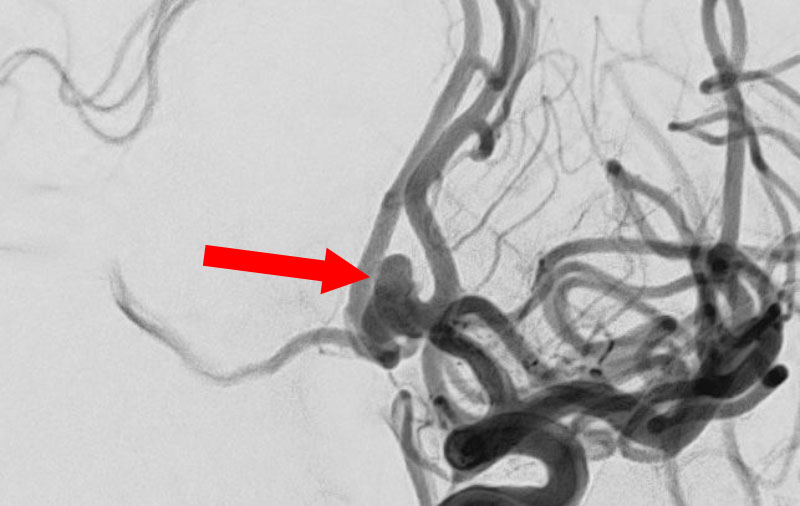

'25年11月

くも膜下出血

破裂性内頚動脈解離

40代

救急外来

No.1594 手術前

No.1594 手術中

No.1594 手術後